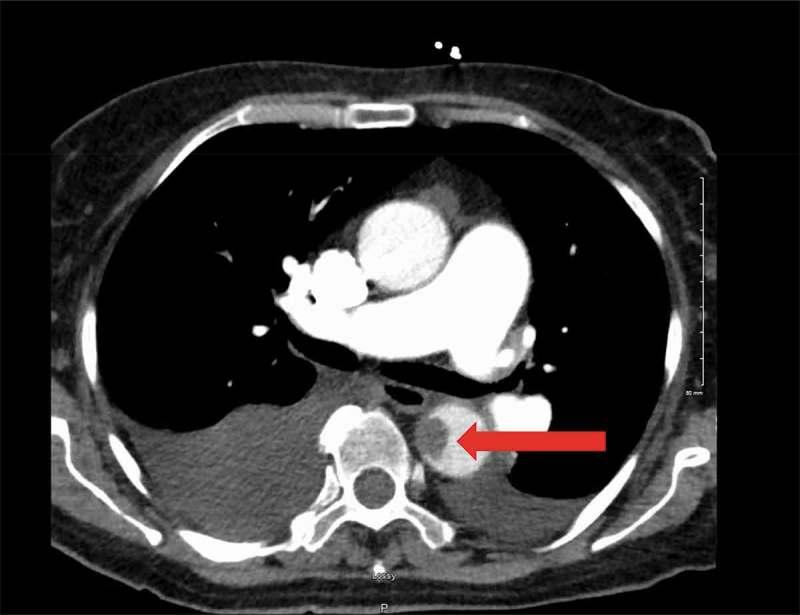

偶然发现的降主动脉血栓:药物治疗与手术治疗的难题

Incidental descending thoracic aortic thrombus: the conundrum of medical versus surgical therapy.

: A mural thrombus in the descending thoracic aorta frequently leads to distal organ and acute limb ischemia, increasing overall morbidity and mortality. Early diagnosis is imperative as thrombi are usually discovered after end organ damage has taken place. The formation of a mural thrombus in descending aorta has not been fully explained; however, the principle of Virchow's triad for thrombogenesis (hypercoagulability, stasis of blood flow and endothelial injury) remains the likely pathophysiologic mechanism. : We present a case of a descending aortic thrombus incidentally detected on computed tomography scan in a 65-year-old female and successfully treated with anticoagulation, preventing subsequent complications. : Suspicion for an aortic thrombus should arise when the origin is not known for acute onset distal limb or organ ischemia.

摘要

降主动脉壁内血栓常导致远端器官和急性肢体缺血,增加总体发病率和死亡率。由于血栓通常在终末器官损伤发生后才被发现,因此早期诊断至关重要。降主动脉壁内血栓的形成尚未完全阐明;然而,血栓形成的魏尔啸三要素(高凝状态、血流淤滞和内皮损伤)原则仍是可能的病理生理机制。我们报告一例65岁女性在计算机断层扫描中偶然发现降主动脉血栓,并通过抗凝治疗成功治愈,预防了后续并发症。当急性发作的远端肢体或器官缺血原因不明时,应怀疑主动脉血栓形成。